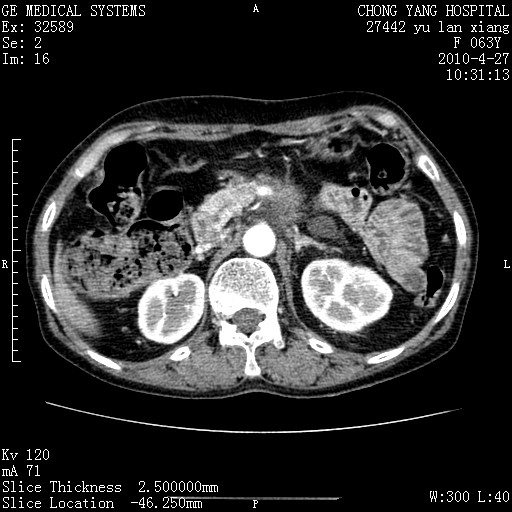

标题: CT26066:F63Y 上腹正中压痛半月,CA199:7400u/ml,MR示胰腺炎伴 [打印本页]

胰腺癌侵犯腹腔动脉干-分支、胃壁、左侧膈肌伴胰周及腹膜后淋巴结转移、胆囊切除术后。

胰腺癌侵犯腹腔动脉干-分支、胃壁、左侧膈肌伴胰周及腹膜后淋巴结转移、胆囊未显影。